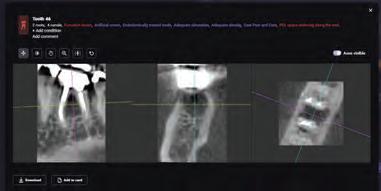

I have been using artificial intelligence tools throughout the examination of all my patients since 2019. I will now present a number of clinical cases from my daily practice, in which artificial intelligence was used as an aid for making informed decisions in diagnosis and treatment planning. It must be said that I deliberately chose routine cases and not “heroic battle tales”. In my presentation below, I will focus on the process

Fig. 1a: A panoramic reformatting of the CBCT scan, made by artificial intelligence, with automatic marking of the inferior alveolar nerve canal.)

Fig. 1b: A panoramic reformatting of the CBCT scan, performed by a human radiographer, with manual marking of the inferior alveolar nerve canal.)

Fig 2: Automatic measurement of the height and width of the alveolar ridge at the designated implantation site (Diagnocat, Diagnocat Inc., USA).

Figure 3a-c: 3D Imaging of the patient’s jaw and teeth. The volume of the CBCT imaging was segmented to STL models, and then the mandible model was made semitransparent to show the IAN canal pathway. (The 3D models were segmented with Diagnocat (Diagnocat Inc., USA) and displayed in the Exocad Webview software (available for free use at webview.dental).

Clinical case no. 1

R., a 40-year-old male, came to the dental clinic due to a previously extracted tooth #19 (ISO 36), and asked for an implant-supported crown to be placed. He was referred for a CBCT at an imaging center, and the resulting 3D volume was uploaded to an artificial intelligence system (Diagnocat, Diagnocat Inc., USA) to perform automatic slicing, detection of the inferior alveolar nerve, and alveolar ridge measurements. Parallel to that, a human radiographer in the imaging center created a manual cross-sections report, that was attached to the 3D DI-COM file.

In the panoramic reformatted image produced as part of the AI-based cross-sections report, it seemed that the pathway of the inferior alveolar nerve forms a loop towards the mandibular foramen, close to the future transplant site. (Fig. 1A) It is unfortunate to mention that a human interpreter

did not mark this loop, (Fig 1B) perhaps due to alternate positioning of the panoramic cross-section.

In light of this discrepancy, I ordered a rendering of the 3D volume to a digital STL model, in order to further appraise the distance between the mandibular foramen and the planned implant placement site. The cross-sectional measurements (Fig. 2) and the segmentation to a 3D model (Fig. 3) were carried out by the same artificial intelligence system (Diagnocat, Diagnocat Inc., USA). These made it possible to understand the exact location of the nerve, and to make sure that it was indeed out of range of danger in this case.